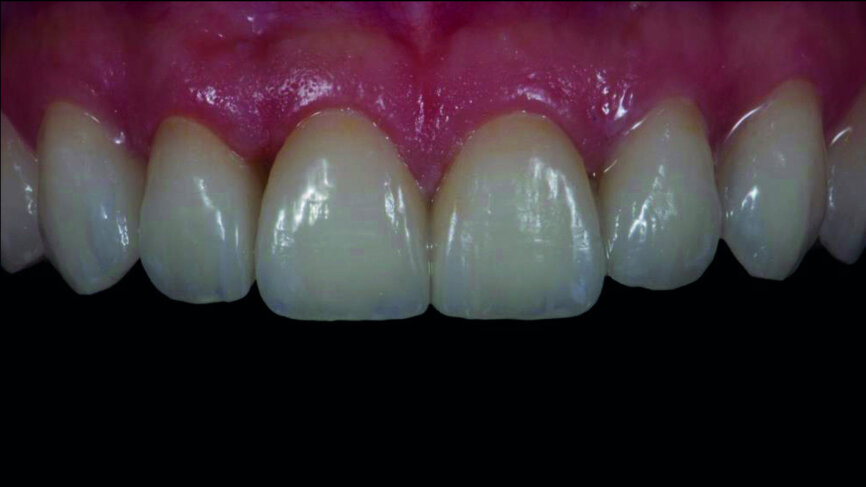

Fig. 17b: Final outcome one week later, frontal view.

Fig. 17c: Lips at rest, exposure of the incisal edges.

The subjective decision of the clinician and the patient was to cement the feldspathic veneers, owing to slight differences in the length of the central incisors between the two sets. Adhesive procedures followed (Figs. 16a–f), and final intraoral and extraoral photographs were captured one week later (Figs. 17a–e).

Intraoral digital scanning is a perfect alternative clinical procedure compared with the conventional impression technique. The digital planning and mock-up procedure is a powerful communication tool for the dentist, although special skills in using computer software are required. Regarding the laboratory workflow, most of the analogue procedures require more time (refractory dies, built-up veneers, adjustments), except the staining/glazing (Figs. 18a & b). Although the aesthetic outcome of the feldspathic veneers was subjectively chosen in this case, the analogue workflow is much more demanding. The digital approach, because of the reduced difficulty, speed, complexity and patient discomfort, tends to be preferable (Figs. 18a & b).